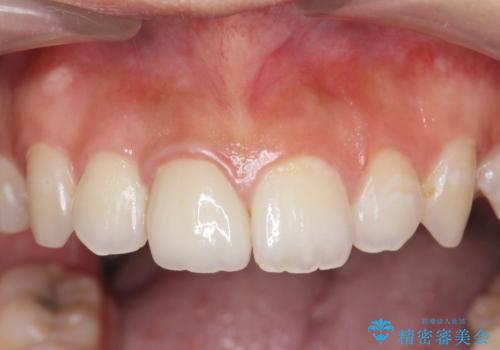

周囲の歯の色調に調和した審美性の高いセラミッククラウンを製作することができました。

前歯の変色をキレイに セラミッククラウン審美治療

ホワイトニングでは、周囲の歯との色調になじむほどには白くできないため、ジルコニアセラミッククラウンを用いて審美性を回復します。